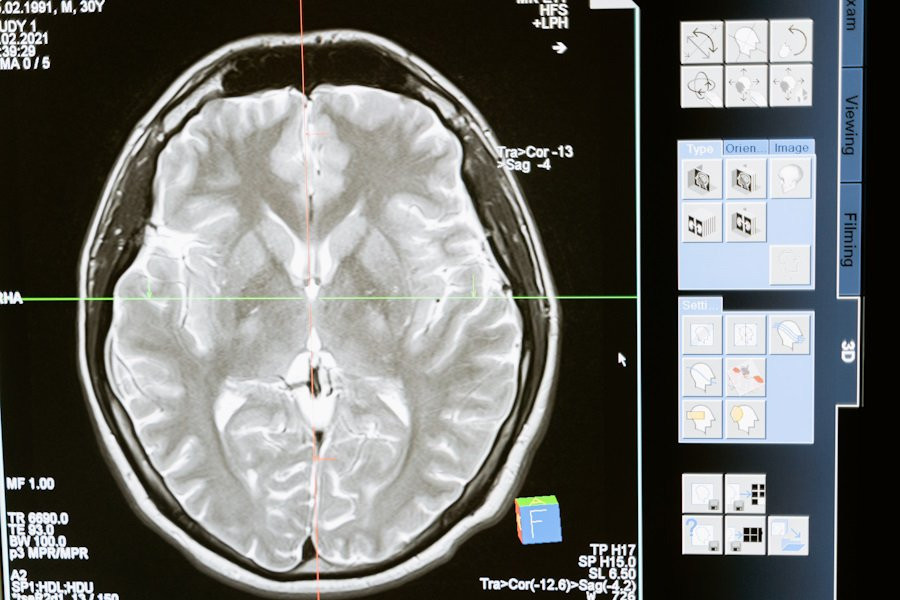

Исследователи из Institute for Basic Science (IBS) (Республика Корея) провели успешные испытания новой методики Magnetogenetic Interface for NeuroDynamics (Nano-MIND), которая позволяет воздействовать на мозг человека без использования имплантатов. Эта технология объединяет магнитные поля и намагниченные наночастицы, что открывает новые возможности для нейромодуляции, сообщает портал Nature.

Методика Nano-MIND использует намагниченные наночастицы и технологию Cre-loxP для избирательной активации генетически закодированных ионных каналов Piezo1 в целевых популяциях нейронов. Это позволяет точно контролировать активность нейронов глубокого мозга как in vitro, так и in vivo.